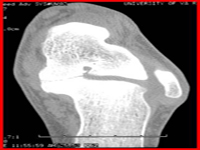

The arch provides an elastic, springy connection between the forefoot and the hind foot. This association safeguards that a majority of the forces incurred during weight bearing of the foot can be dissipated before the force reaches the long bones of the leg and thigh. However there are no reports that conclusively prove that children with flat feet have an increased incidence of foot pain or knee pain. Shoe inserts may not help in the development of arches. There are many studies performed to prove this.Studies have shown thatwearing shoes throughout early childhood can be detrimental to the development of a normal or a high medial longitudinal arch. Hence children should be encouraged to play barefooted on various surfaces of terrain. Slippers and sandals are less harmful compared to closed-toe shoes. Hence no special treatment is usually required for such feet. You need to consult a doctor if there is pain in foot, outward tilting of the heel, difficulty with shoes or awkwardness in walking. Physiological flat feet should be distinguished from congenital vertical talus in which children have a convex lower border of foot. Plaster treatment and early surgical intervention is required in these children. Another common cause for adolescent flat foot is development of talonavicular or talo calcaneal bar. Two bones are joined by abnormal bar which limits movement of the bones. The treatment of this condition includes surgical excision of bar.